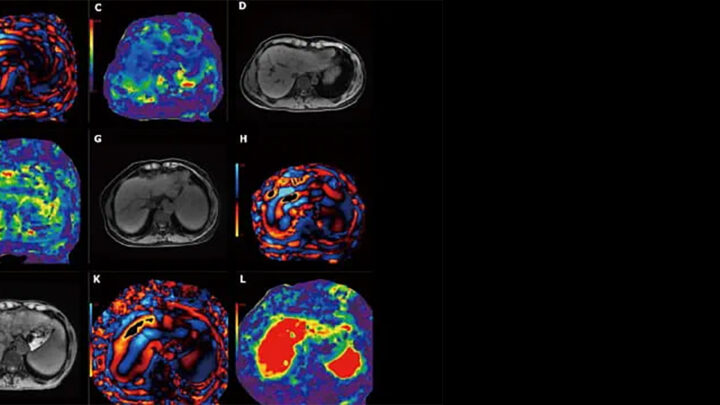

Imagen: https://diarioelectronico.com/2025/10/03/alza-enfermedades-cardiovasculares-jovenes-prevenir-infarto-la-primera-causa-muerte-chile/ De enero a junio 2025 se registraron 402 320 defunciones. Fuente: INEGI El Instituto Nacional de Estadística y Geografía…